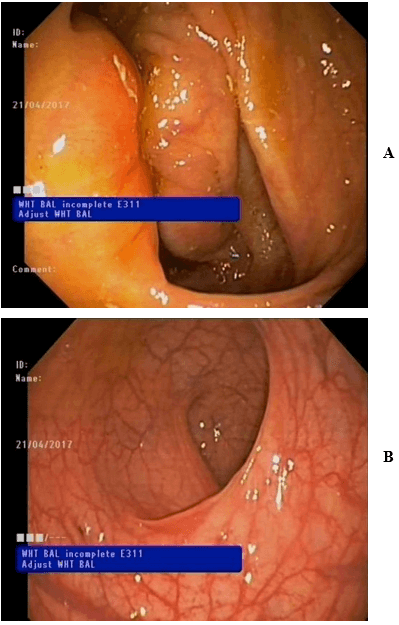

A colonoscopy was done, and 3 polyps were founded in the large bowel (Figures 1A & 1B). The biopsies were stained with hematoxylin and eosin and in two of the three sections, tubular polyps were described. The third one showed a histopathological picture compatible with MALT lymphoma (Figures 2A, 2B, 2C & 2D). The whole lesion was removed. Immunohistochemistry profile (CD20+, CD3-, BCL2+, CD43+, BCL6-, CD5-, CD10-, CD23- and cyclin D1-) and FISH (rearrangement of 18q21 evaluated by break-apart probe) was accorded to the diagnosis. Bone marrow trephine biopsy did not show infiltration or abnormal findings, and TC body scan was normal.

Figure 1: A) & B) Tissue of polypoid appearance, 44 cm from the anal margin.